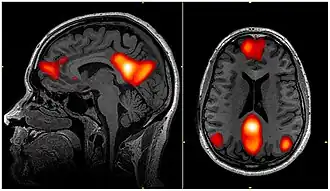

fMRI scan showing regions of the default mode network; the dorsal medial prefrontal cortex, the posterior cingulate cortex, the precuneus and the angular gyrus

In neuroscience, the default mode network (DMN), also known as the default network, default state network, or anatomically the medial frontoparietal network (M-FPN), is a large-scale brain network primarily composed of the dorsal medial prefrontal cortex, posterior cingulate cortex, precuneus and angular gyrus. It is best known for being active when a person is not focused on the outside world and the brain is at wakeful rest, such as during daydreaming and mind-wandering. It can also be active during detailed thoughts related to external task performance.[3] Other times that the DMN is active include when the individual is thinking about others, thinking about themselves, remembering the past, and planning for the future.[4][5] The DMN creates a coherent "internal narrative" central to the construction of a sense of self.[6]